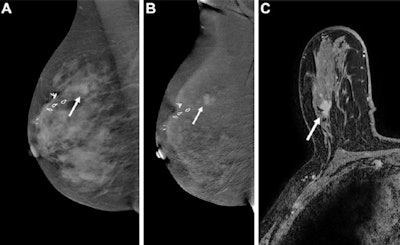

CEM images (A, B) and an MRI scan (C) show true-positive findings in a 73-year-old woman with a personal history of right breast ductal carcinoma in situ (DCIS) treated with lumpectomy and newly diagnosed left breast invasive lobular carcinoma (not shown), who presented for contralateral right breast screening. (A) Mediolateral oblique low-energy and (B) mediolateral oblique recombined CEMs of the right breast show an irregular contrast-enhanced mass with irregular margins in the upper outer quadrant (arrows). (C) Axial contrast-enhanced breast MRI sequence shows an irregular contrast-enhanced mass with irregular margins that is suspicious for cancer in the upper outer quadrant of the right breast (arrow). Pathology revealed recurrent invasive ductal carcinoma and DCIS, Nottingham grade I, that was estrogen receptor positive, progesterone receptor positive, and human epidermal growth factor receptor 2 (HER2) receptor negative. Images courtesy of RSNA.In their single-institution, prospective, blinded reader study, the researchers included women who were referred for breast MRI between 2018 and 2021. CEM was performed within 14 days of standard MRI, while abbreviated MR images were produced from standard MR images. Two readers independently interpreted each CEM and abbreviated MR image after a washout period.